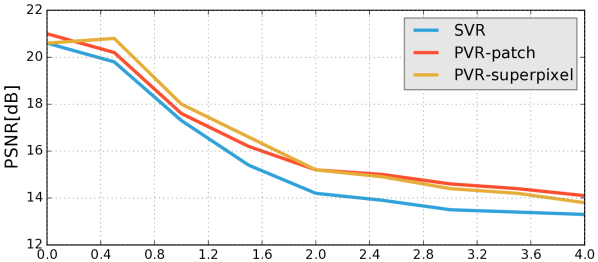

Reconstruction of Fetal Organs: Exemplary PVR and SVR reconstructions under motion introduced by kicking of the fetus are shown in Fig. 11. PVR reconstruction results show an improved visual appearance and less blurring in the region with severe motion artifacts (arrow). An example of a challenging clinical case with a kidney malformation in one of twin fetuses, is shown in Fig. 8. Our clinical partners confirmed that such complications are easier to examine and to quantify after PVR-based reconstruction.